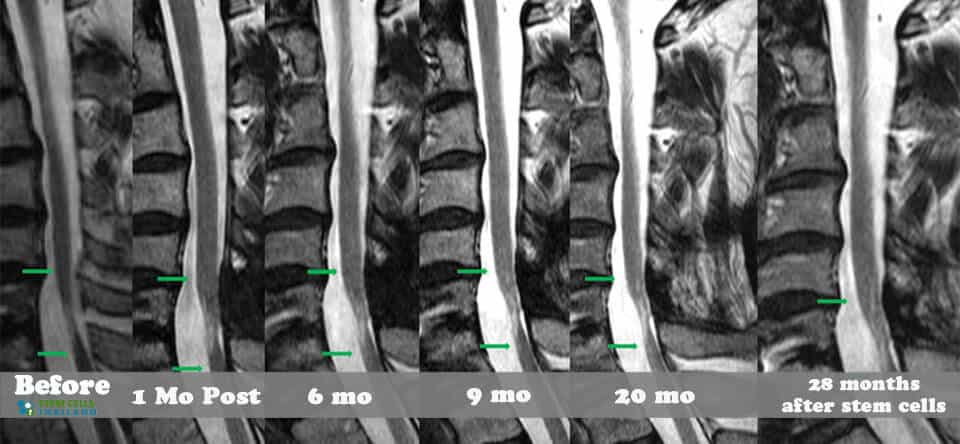

組織、軟骨或韌帶的新損傷對干細胞治療的反應要好得多。治療后的康復需要大量的奉獻和康復訓練。初次治療后約2-3個月,身體改善明顯,且效果是永久性的。[2]